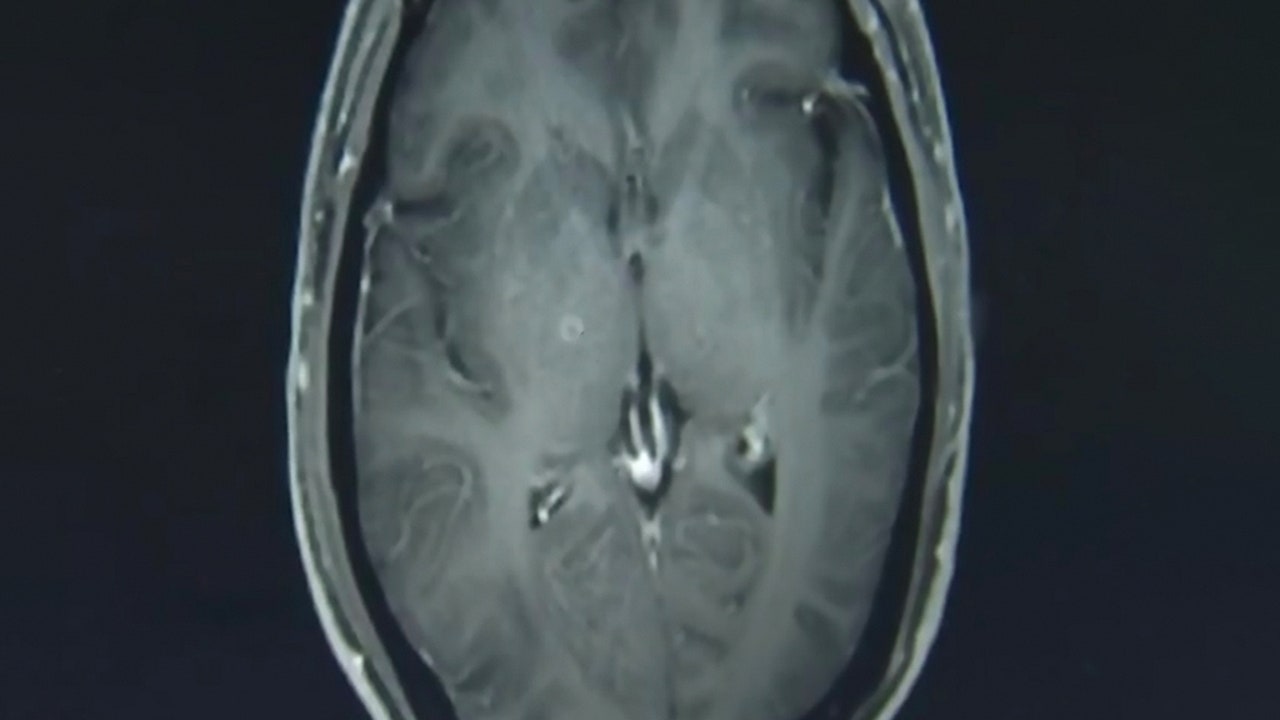

The tapeworms, seen above in a scan of Zhu Zhonfa's brain, entered his body through his digestive system after he ate undercooked pork. (AsiaWire)

A 43-year-old man in China who was suffering from seizures and loss of consciousness went to the doctor after his symptoms persisted for several weeks, only to discover that he had hundreds of tapeworms in his brain and chest, reports say.

Jianrong explained that the larvae entered Zhongfa’s body through the digestive system and traveled upward through his bloodstream. He was officially diagnosed with cysticercosis and neurocysticercosis, and given an antiparasitic drug and other medications to protect his organs from further damage, according to AsiaWire.